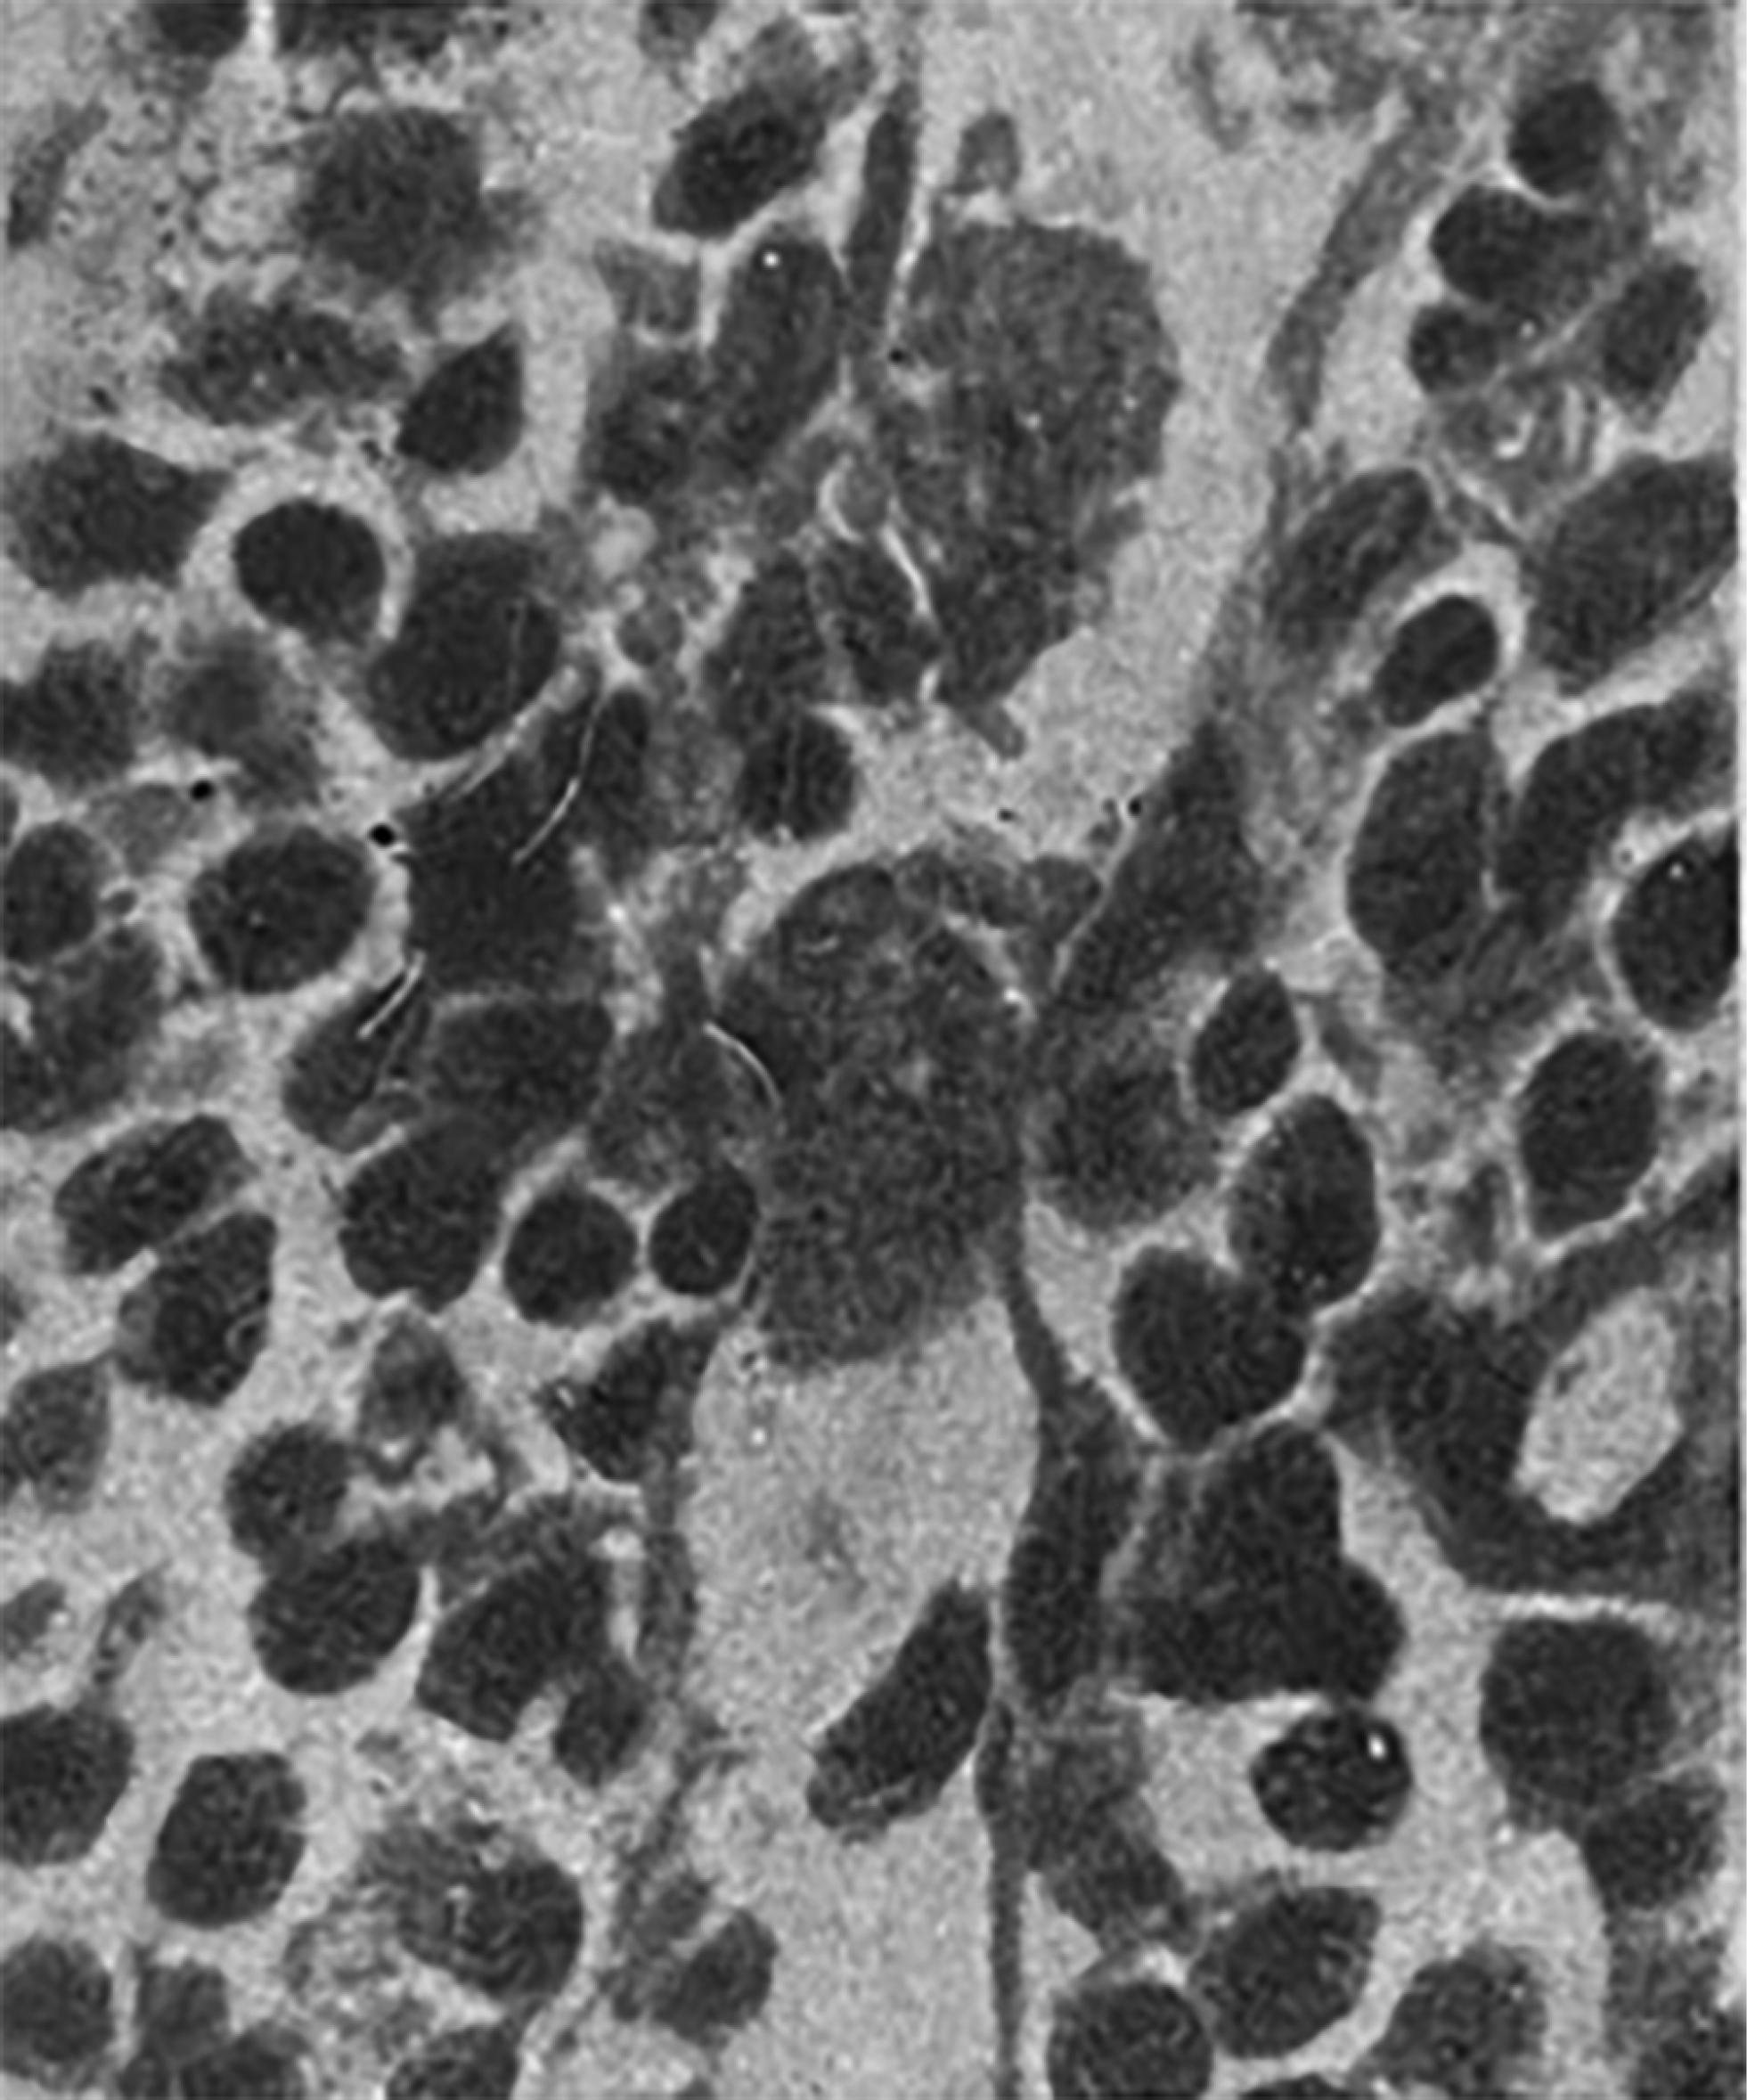

Особое внимание Я.Л. Рапопорт уделял морфологической основе механизмов нервной и гуморальной регуляции иммуногенеза. Он подчёркивал особую значимость изучения роли лимфатического аппарата и ретикуло-гистиоцитарной системы (в терминах тех лет) как центра продукции антител. Им получены уникальные гистологические препараты тканей экспериментальных животных, сенсибилизированных экзогенными антителами (рис. 6) [6].

Рис. 6. Лимфатический узел морской свинки на 20-й день после введения дифтерийного анатоксина. Резкое набухание синусовых клеток, ретикулогистиоцитарная гиперплазия плазмоцитов [8].

Fig. 6. Lymph node of a guinea pig on the 20th day after administration of diphtheria toxoid. Sharp swelling of sinus cells, reticulohistiocytic hyperplasia of plasma cells [8].